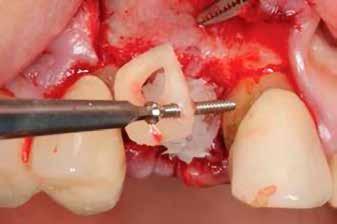

3. a–b ábrák: Fogeltávolítást követő alveolus prezerváció. – 4. a–b ábrák: Az implantátumok beültetése.

A fogak eltávolítása minimálinvazív módon történt, amelynek során a parodontális rostokat egy periotom segítségével átvágtuk, így lebenyes feltárásra nem volt szükség (3. a–b ábrák) . Az implantátumokat a frissen eltávolított fogak alveolusaiba ültettük be. A foghúzást követően minden alveolust alaposan ellenőriztünk az endodontiai, vagy parodontális eredetű gyulladásos szövetmaradványok eltávolítása érdekében, majd fiziológiás sóoldattal bőségesen átöblítettük. Megfelelő előfúrást követően a kerámiaimplantátumokat 30 fordulat/perc sebességgel és 35 Ncm behajtási nyomatékkal helyeztük be (4. a–b ábrák) . A réseket csontpótlóval töltöttük ki (Maxresorb ® 0,5–1,0 mm szemcseméret, 0,5 cm 3 térfogat, Straumann ®; 6. ábra ).